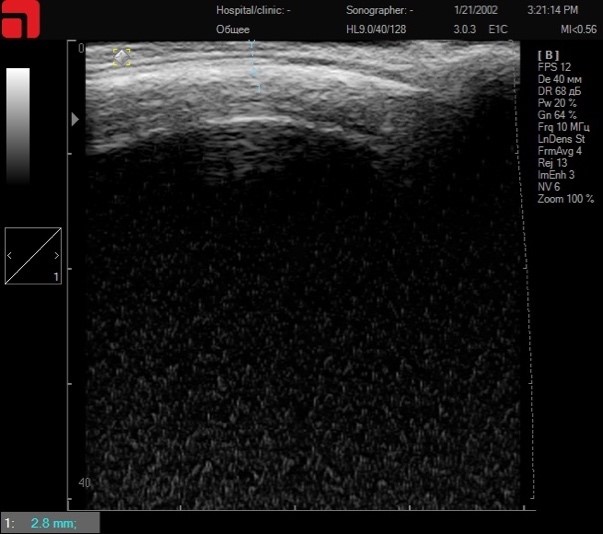

Область лба – это участок, в котором часто встречается неверное составление протокола процедуры из-за переоценки глубины возможной работы (Рис.5.). Задача ультразвукового сканирования – определить, на какой глубине заканчиваются мягкие ткани и начинается лобная кость (os frontale). К примеру, на данной сканограмме видно, что лобная кость начинается на глубине 2,8 мм. Следовательно, для эффективной и безопасной работы будет использоваться манипула 1,5 мм S7.

Сканирование области лба

Рис. 5. Сканирование области лба.